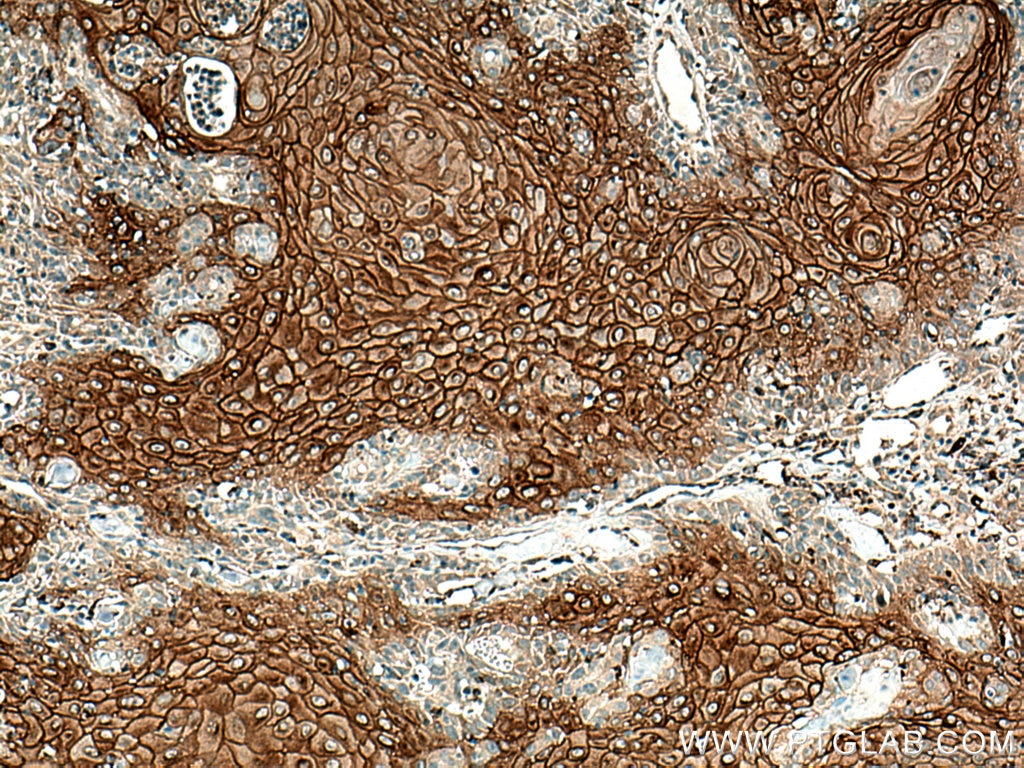

| Positive IHC detected in | mouse skin tissue, human skin cancer tissue, rat skin tissue Note: suggested antigen retrieval with TE buffer pH 9.0; (*) Alternatively, antigen retrieval may be performed with citrate buffer pH 6.0 |

24587-1-AP targets DSG1 in WB, IHC, IF/ICC, ELISA applications and shows reactivity with human, mouse, rat samples.

Desmosomes are cell-cell junctions between epithelial, myocardial, and certain other cell types. Desmosomal cadherins, consisting of four desmogleins (DSG1-4) and three desmocollins (DSC1-3) in humans, mediate adhesion through calcium-dependent homophilic/heterophilic interactions. DSG1 is a single-pass transmembrane glycoprotein highly expressed in the epidermis and localized primarily within the suprabasal epithelial layers (PMID: 16286477; 24220297). DSG1 mediates intercellular adhesion and is crucial in maintaining epidermal integrity and barrier function (PMID: 23974871). It is also involved in epithelial cell differentiation (PMID: 23524961). Mutations in the DSG1 gene can cause the autosomal dominant disorder to striate palmoplantar keratoderma and a syndrome featuring severe dermatitis, multiple allergies, and metabolic wasting (SAM syndrome) (PMID: 29315490; 23974871).